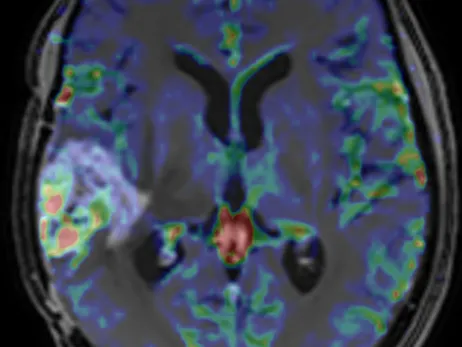

Brain Tumours Imaging: Classification, Diagnosis and Treatment Follow up

This brain imaging course will cover almost all tumours inside the skull and especially intends to give Radiologists the right tools to make the differential and correct diagnosis of a tumour. Follow-up imaging in glial tumours may also be troublesome in many cases and this topic will be discussed in all aspects to build a guide for all attendees when reporting the follow-up of brain tumour cases.

The advantages of each imaging technique in the differential diagnosis of brain tumours will be presented in detail. The case discussions will help attendees to understand how to approach brain tumour cases and will improve their skills for the future when reporting real –life daily cases. The case discussions will include some common and uncommon cases, but each one of them will have a message for the attendees in order to help them improve their experience on brain tumour imaging.